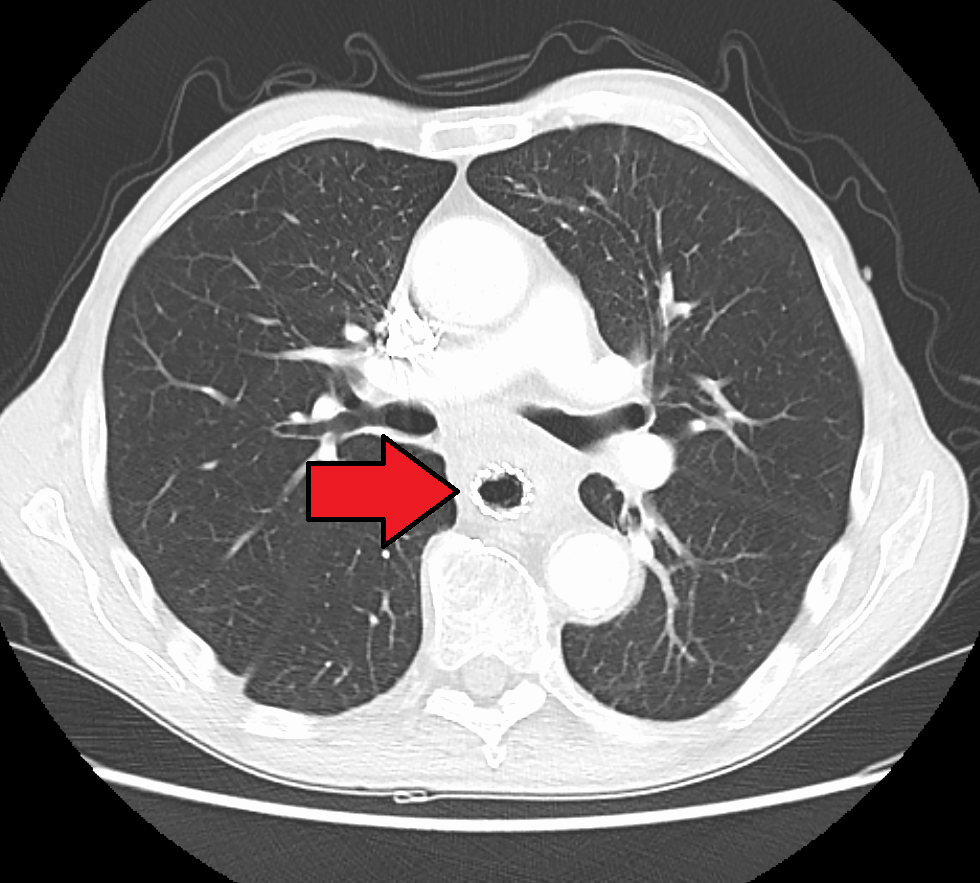

바륨 삼킴 검사나 바륨 식사 검사에서 폐쇄성 종양을 의심할 수 있지만, 진단은 내시경을 이용한 검사로 하는 것이 가장 정확하다. 내시경 검사는 광원과 카메라가 달린 유연한 관을 식도로 통과시켜 식도벽을 검사하는 것으로, 식도위십이지장내시경검사라고 한다. 그런 다음 의심스러운 병변의 조직을 채취하여 악성 징후가 있는지 조직학적으로 검사한다.[140][141]암이 얼마나 퍼졌는지 평가하려면 추가 검사가 필요하다. 흉부, 복부 및 골반의 컴퓨터 단층 촬영(CT)을 통해 암이 인접 조직이나 멀리 떨어진 장기(특히 간 및 림프절)로 퍼졌는지 여부를 평가할 수 있다. CT 스캔의 민감도는 일반적으로 1cm 보다 큰 종괴(예: 림프절 비대 또는 관련 장기)를 감지하는 능력에 의해 제한된다.[142] 양전자 방출 단층 촬영(PET)은 질병의 범위를 추정하는 데 사용되며 CT 단독보다 더 정확한 것으로 간주된다.[143] 새로운 검사 기구인 PET/MR은 PET/CT와 비교하여 타당성이 높고 상관관계가 좋은 수술 전 병기 결정에서 유망한 결과를 보여주었다.[144] 환자에 대한 방사선량을 낮추면서 조직 분화를 향상시킬 수 있다. 식도 내시경 초음파는 종양의 침범 수준과 국소 림프절로의 전이 가능성에 관한 병기 정보를 제공할 수 있다.

4. 2. 추가 검사 (병기 결정)

암의 확산 정도를 평가하기 위해 추가 검사가 필요하다. 흉부, 복부 및 골반의 컴퓨터 단층 촬영(CT)을 통해 암이 인접 조직이나 멀리 떨어진 장기(특히 간 및 림프절)로 퍼졌는지 여부를 평가할 수 있다. CT 스캔의 민감도는 일반적으로 1cm보다 큰 종괴(예: 림프절 비대 또는 관련 장기)를 감지하는 능력에 의해 제한된다.[140][141] 양전자 방출 단층 촬영(PET)은 질병의 범위를 추정하는 데 사용되며 CT 단독보다 더 정확한 것으로 간주된다.[142] PET/MR은 PET/CT와 비교하여 타당성이 높고 상관관계가 좋은 수술 전 병기 결정에서 유망한 결과를 보여주는 새로운 검사 기구이다.[143] PET/MR은 환자에 대한 방사선량을 낮추면서 조직 분화를 향상시킬 수 있다. 식도 내시경 초음파는 종양의 침범 수준과 국소 림프절로의 전이 가능성에 관한 병기 정보를 제공할 수 있다.5. 유형